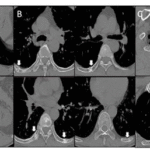

Pediatric liver transplantation (pLT) is the standard treatment forend-stage liver disease in children. Perioperative cardiopulmonary complications, including severe infection and respiratory failure, sometimes require extracorporeal membrane oxygenation (ECMO).